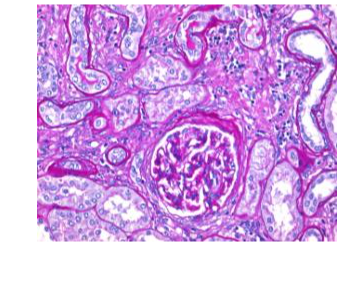

Schiff‘s reagent for the periodic acid Schiff, or PAS reaction, is used for the detection of mucopolysaccharides, glycogen, muco- and glycoproteins, glyco-, phospholipids, basal membranes and collagen. With Schiff's reagent aldehydes give a bright red color reaction, thus in combination with the periodic acid the nuclei appear blue. 500 ml are sufficient for approx. 2500 - 3000 stainings. It is registered as IVD and CE certified product and can be used for clinical diagnostics.